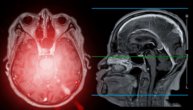

Kad ga vidite danas, teško biste pomislili da je pre osam godina bio sekundu daleko od toga da sve izgubi. Ima tih, miran glas i stidljivu naviku da levu ruku drži malo drugačije, kao da je štiti. U njegovom pogledu vidi se ono što preživljeni moždanog udara često imaju – zahvalnost što je tu i tuga zbog onoga što više nikada neće biti isto.

– Oko podne sam osetio da mi nešto kreće niz levu ruku. Kao trnci, pa slabost. Uhvatio sam kutiju da je podignem, ali prsti me nisu slušali. Hteo sam da kažem kolegi da pozove hitnu pomoć, ali nisam umeo da sastavim rečenicu. Jezik me nije slušao. U tom trenutku sam znao da je nešto ozbiljno.

– Kad su mi rekli brojke, nisam mogao da verujem. Ja koji sam jutros trčao, radio, sve kako treba. A onda moždani udar. Nisam razumeo kako se to dogodilo - kaže Marko.

– Danas mi je leva ruka utrnuta. Kao da nije moja. Stopalo isto. Hodam, radim, ali osećaj nije isti. Osam godina je prošlo, a nervi se nisu oporavili - kaže Marko i dodaje: